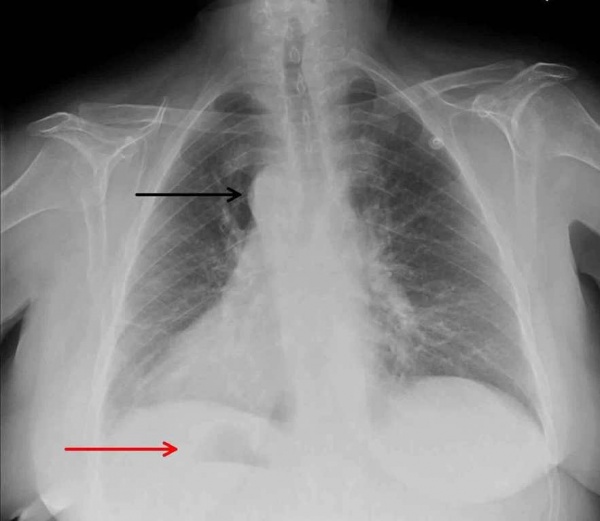

У детей в возрасте 1-1,5 месяцев по ЭКГ обнаруживаются признаки перегрузки и гипертрофии правых отделов сердца. При оценке рентгенографии грудной клетки высокоспецифичными признаками транспозиции магистральных сосудов являются: кардиомегалия, характерная конфигурация тени сердца яйцеобразной формы, узкий сосудистый пучок в переднезадней проекции и расширенный в боковой проекции, левое положение дуги аорты (в большинстве случаев), обеднение рисунка легких при стенозе легочной артерии или его обогащение при дефектах перегородки.

Рентгенографическая картина легких может меняться по мере роста ребенка. У новорожденных легочный рисунок нормальный. К концу первого месяца в большинстве случаев отмечается усиление легочного рисунка по артериальному типу (особенно при сопутствующих ОАП и ДМЖП), реже возникают симптомы венозного застоя. Тень сердца несколько расширена в поперечнике, имеет характерный овоидный вид («яйцо, лежащее на боку») (рис. 4-3, А). Сосудистый пучок в передне-задней проекции узкий, в боковой — широкий. При сопутствующем ДМЖП специфический характер конфигурации сердца теряется.